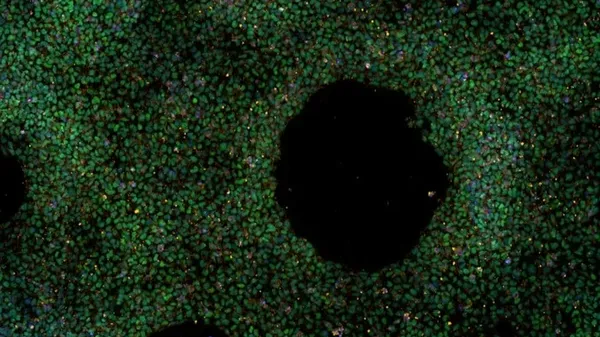

La fibrosi cistica fa sentire il suo peso anche sull ’età biologica dell’organismo, facendolo invecchiare di tre-quattro anni , ma è anche possibile far regredire questo processo . Lo indica la ricerca condotta in Italia, presso il Ceinge-Biotecnologie Avanzate ‘Franco …